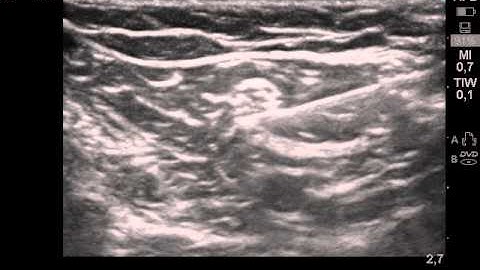

Infiniti Plus In-Plane Needle Guidance